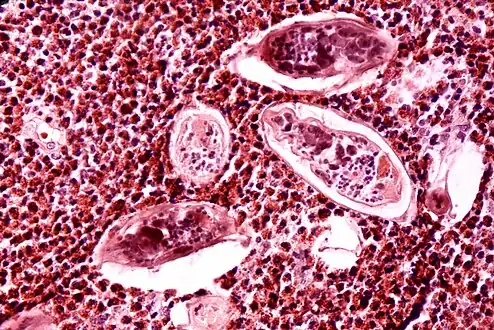

High-powered detailed micrograph of Schistosoma parasite eggs in human bladder tissue

S. japonicum eggs in hepatic portal tract